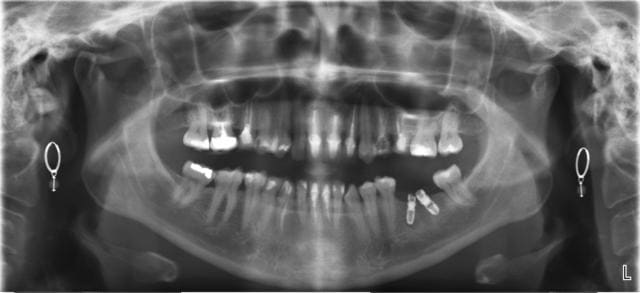

Sérieusement, une 47, avec ouverture très limitée, et muscle de la joue très costaux...j'y voyais rien !

Heureusement, la 46 avait déjà une endo !

Soyez indulgent, la final n'est pas si mal...un poil trop angulé...mais bon...

t'avais forcément envie qu'un badabeu te la pose non sinon tu ne l'aurais pas posté cette pano boucles d'oreillée

C'est un cas (à ne pas reproduire systématiquement) mais "d'école" 2 implants pour une dent le plus proche de la réalité. Explication de l'interet de la divergence et des possibilté offerte par l'asence de vis etc...

En fait spécificité Leone et pour mes communications.

Oui et non c'était plus pour la "déconne" avec notre ami canadien. Au bout d'un moment on s'ennuie à planter tjrs droit! On sait faire maintenant et ça fait pas avancer le schmilblick.

pour marcus même dans la nature t'as souvent vu pareille divergence ?

la résultante des forces oclusales sur ton bazar au final est elle si différente que si tu les avait planté droit

il semblerait que physiquement parlant si tu fais la résultante des forces un implant central "droit" serait identique donc tu fais du surtraitement en en mettant deux dans des axes volontairement choisis pour montrer qu'on peut toujours s'en sortir avec le systême.